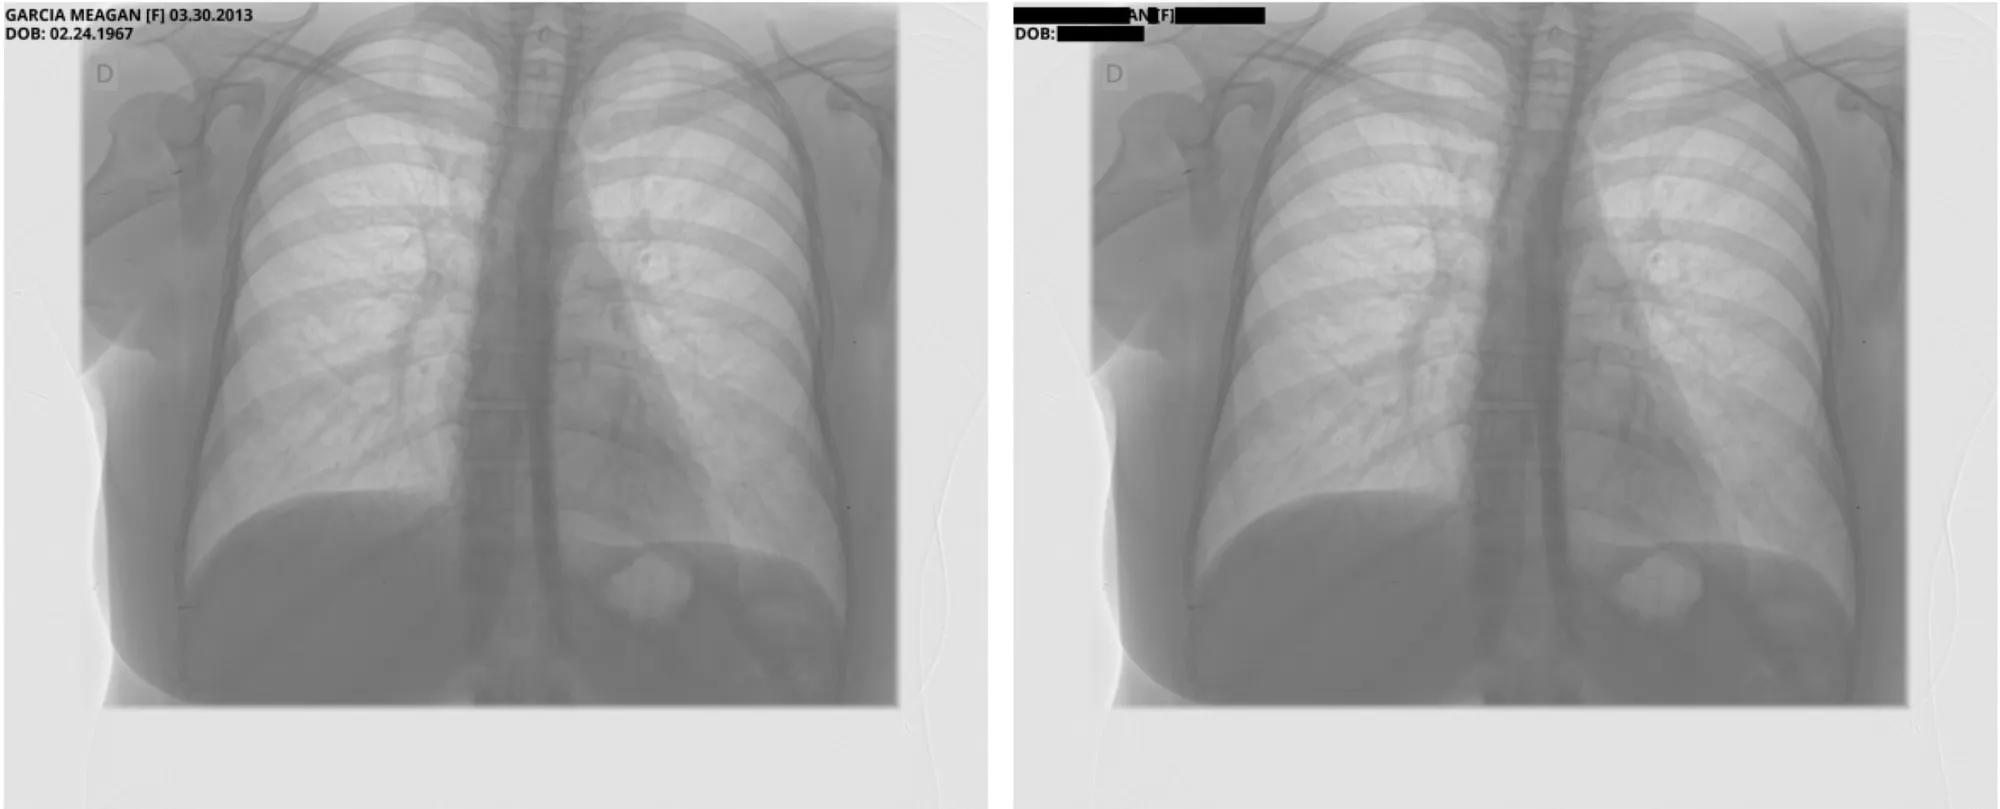

Pixel DeIdentification Original ( Left ) -> DeIdentified ( Right )

Reference : MIDI-B Pixel Metadata DeIdentification Notebook

Metadata DeIdentification Original ( Left ) -> DeIdentified ( Right )

Sample Pixel Result 1

Sample Pixel Result 2

Sample Pixel Result 3